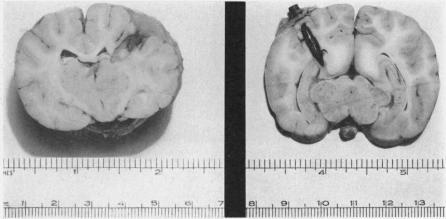

Pilcher C

Ann Surg. 1936 Feb;103(2):173-98. doi: 10.1097/00000658-193602000-00003.